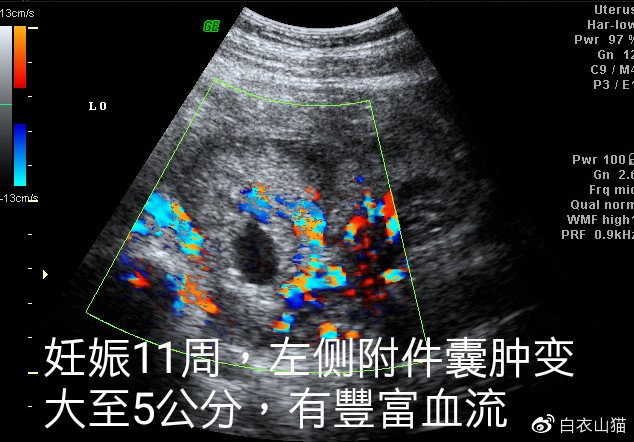

左侧附件囊肿

11周时候左侧附件囊肿增大到了5厘米。

孕11周的时候,小兰到宝山医院产科门诊复查,医生发现胎儿在宫内心跳正常,小兰的左侧附件囊肿增大到了5厘米。毕竟小兰已经怀孕了,而且没有什么不舒服,因此,医生暂时没有处理小兰的左侧附件囊肿。